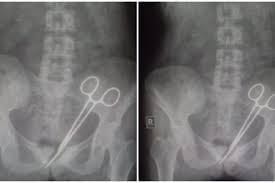

ଡାକ୍ତର ସର୍ଜରୀ ଦ୍ୱାରା ଜଣେ ମହିଳାଙ୍କର ଆପେଣ୍ଡିକ୍ସ କାଢ଼ିଥିଲେ। ତେବେ ସିକ୍କିମର ମହିଳା ଜଣଙ୍କ ଅପରେସନ ପରେ ମଧ୍ୟ ଯନ୍ତ୍ରଣାରୁ ମୁକ୍ତି ପାଇ ନଥିଲେ। ଦୀର୍ଘ ୧୨ ବର୍ଷ ଧରି ତାଙ୍କୁ ଏପରି ଯନ୍ତ୍ରଣା ଭୋଗିବାକୁ ପଡ଼ିଥିଲା। ଅନେକ ଡାକ୍ତରଙ୍କୁ ସେ ନିଜର ଚିକିତ୍ସା କରିବାକୁ କହିଥିଲ ହେଁ କିଛି ବି ଲାଭ ମିଳି ନଥିଲା।ଡାକ୍ତର ତାଙ୍କ ଯନ୍ତ୍ରଣାର କାରଣ ଜାଣି ପାରିଛନ୍ତି। ଯନ୍ତ୍ରଣାର କାରଣ ଜାଣିବା ପରେ ମହିଳା ଓ ତାଙ୍କ ପରିବାର ସମେତ ସେ ଚିକିତ୍ସା ପାଇଁ ଯାଇଥିବା ଡାକ୍ତର ପୂରା ଚକିତ ହୋଇ ଯାଇଛନ୍ତି। ୪୫ ବର୍ଷୀୟ ମହିଳାଙ୍କ ତଳି ପେଟରୁ ବାହାରିଛି ଅପରେସନ ବେଳେ ବ୍ୟବହାର ହେଉଥିବା ଗୋଟିଏ କଇଁଚି। ୨୦୧୨ରେ ମହିଳାଙ୍କ ଅପରେସନ ଯେଉଁ ହସ୍ପିଟାଲର ଡାକ୍ତରମାନେ କରିଥିଲେ, ସେମାନେ ତାଙ୍କ ତଳି ପେଟରେ ଏହାକୁ ଛାଡ଼ି ଦେଇଥିଲେ। ସେବେଠାରୁ କଇଁଚିଟି ତାଙ୍କ ତଳି ପେଟରେ ରହିଥିଲା। ମହିଳାଙ୍କ ସ୍ୱାମୀ କହିଛନ୍ତି ଯେ ୨୦୧୨ରେ ଗ୍ୟାଙ୍ଗଟକର ଏସଟିଏନଏମ ହସ୍ପିଟାଲରେ ଆପେଣ୍ଡିକ୍ସ ଅପରେସନ ହୋଇଥିଲା। ତଥାପି ତାଙ୍କ ପତ୍ନୀ ସବୁବେଳେ ତଳି ପେଟରେ ଯନ୍ତ୍ରଣା ଅନୁଭବ କରୁଥିଲେ। ୧୨ ବର୍ଷ ମଧ୍ୟରେ ସେ ଅନେକ ଡାକ୍ତରଙ୍କ ପରାମର୍ଶ ନେଇଥିବା ବେଳେ ସମସ୍ତେ ମେଡିସିନ ଦେଇଥିଲେ। ତଥାପି ସମୟକ୍ରମେ ଯନ୍ତ୍ରଣା ଅନୁଭବ ହେବାରେ ଲାଗିଥିଲେ। ଶେଷରେ ଅକ୍ଟୋବର ୮ରେ ସେ ପୁଣି ପତ୍ନୀଙ୍କୁ ଧରି ଏସଟିଏନଏମ ହସ୍ପିଟାଲକୁ ଯାଇଥିଲେ। ସେଠାରେ ଭଲ ଭାବେ ଏକ୍ସ ରେ କରାଯିବାରୁ ମହିଳାଙ୍କ ତଳି ପେଟରେ ଥିବା କଇଁଚି ସମ୍ପର୍କରେ ଜଣାପଡ଼ିଥିଲା।ଏକଥା ଜଣାପଡ଼ିବା ପରେ ଗୋଟିଏ ବିଶେଷଜ୍ଞ ଟିମ ମହିଳାଙ୍କ ତଳି ପେଟରୁ ଅପରେସନ ଦ୍ୱାରା କଇଁଚିକୁ ବାହାର କରିଛନ୍ତି। ଏବେ ମହିଳାଙ୍କ ଅବସ୍ଥା ସ୍ଥିର ରହିଛି ଓ ସେ ସୁସ୍ଥ ମଧ୍ୟ ହେଉଥିବା ଜଣାପଡ଼ିଛି।